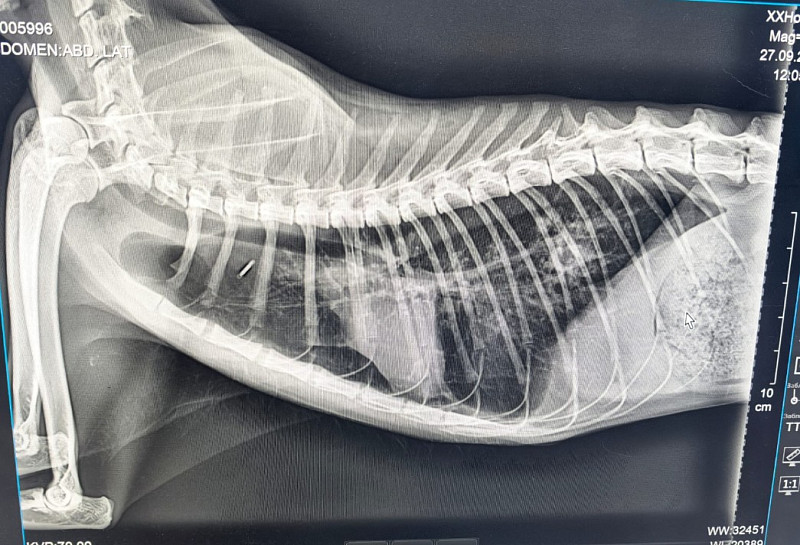

Рентген ориентальной кошки

Помогите разобраться, что с легкими у моего кота, так как вразумительного ответа получить в ветклинике не смог. Может это может то, может астма, может ещё что, а что не понятно. Кот периодически кашляет, хрипит, но в целом, состояние нормальное, нос мокрый, температуры нет, играет. Кашель уже достаточно длительно время стали замечать за ним. Может неделю не кашля, две, хотя может и на глаза нам не попадался. Также могу направить видео его поведения при приступах

здравствуйте, точный диагноз по рентгену невозможен, в данном случае можно только диагностировать прогрессирующее хроническое заболевание бронхов/легких. Для уточнения диагноза необходимо также сделать узи/КТ грудной полости, также нужны анализы крови. Без дополнительной диагностики могут быть назначены только препараты для облегчения кашля. У кошек они как правило в ингаляционной форме.